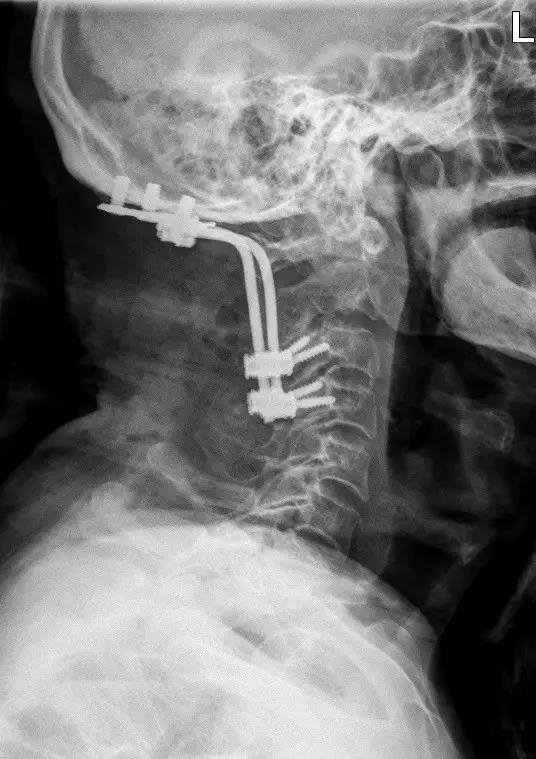

来自江苏的宣爷爷在一双儿女的陪同下,不辞辛苦来到钱列副主任的专家门诊,他双眉紧锁:“钱主任啊,我脖子疼的要命啊,两只手也麻,晚上睡也睡不着,您有办法救救我吗?”通过仔细体格检查并结合颈椎核磁共振,钱列医生发现他的颈椎椎体里长了肿瘤,已经侵蚀了两个椎体(C1、C2),考虑恶性肿瘤可能性大,如不及早手术治疗,病情会进一步恶化。然而,患者已经93岁高龄,手术和麻醉存在一定风险。但是,面对患者的诉求和愁眉不展的家属,钱列医生还是决定积极治疗:“老先生,不用担心,我们一定尽力为你诊治。”

患者入院后,脊柱外科医疗团队积极组织术前各科会诊及完善相关检查,老先生既往体健,无高血压、糖尿病等内科慢性病,术前全身检查未发现原发肿瘤病灶,全科在疑难病例讨论后,制定了最合适的手术方案。经过一系列的缜密准备,钱列副主任、劳立峰主治医师在麻醉科、手术室、重症医学科的保驾护航下,为患者实施了颈椎后路肿瘤切除减压内固定术,手术仅用时2个多小时,术中出血量不到100ml。术后症状逐渐缓解,病理提示C2恶性肿瘤,已联系肿瘤科、放疗科进一步诊治。